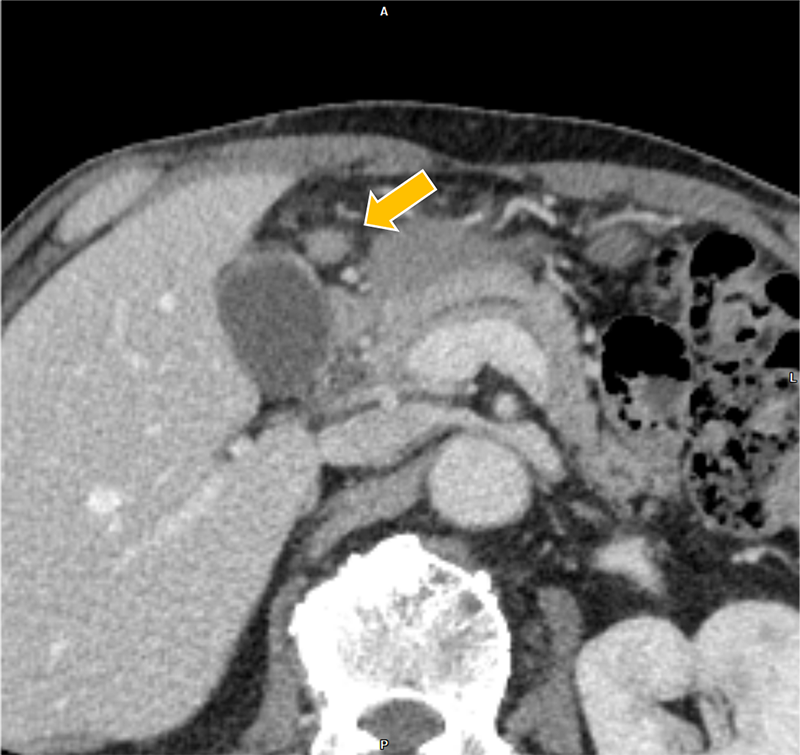

膀胱癌の治療経過観察中、胆嚢癌が疑われ、術前精査目的に肝ダイナミックCTが施行された。胆嚢底部に長径30mm程の腫瘤を認めた。また、胆嚢左側や背側にリンパ節転移を疑う造影結節を認めた。さらに、同CTで前立腺左葉から直腸左側にかけての膿瘍形成が指摘され、後の精査でBCG注入療法に伴う骨盤内BCG感染症が明らかとなった。膿瘍の治療過程で腹膜播種が出現、胆嚢癌は化学療法の方針となった。